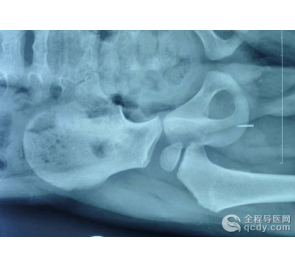

15岁的小刚(化名)家住沛县,8月10日,因和家人怄气,吞下了一枚缝被子的钢针(长约5.6厘米)。当地医院检查发现,钢针已经插入患者肺部,由于条件有限,当地医院劝其家人送往徐州市第一人民医院。接到电话后,徐州市第一人民医院呼吸一科主任任光明,立刻通知该院医务处、胸外科、耳鼻喉科,做好术前准备。当天18时,患者到达医院。

在相关科室的配合下,任光明主任为患者实施了纤维支气管镜下支气管异物取出术。术中,任光明发现钢针已经向下移动了6厘米,如不及时取出,可能戳伤周围组织和器官,严重的可导致死亡。在相关科室的配合下,任主任小心地将钢针一点点的上移,约20分钟将其取出,避免了患者开胸的痛苦。目前,患者正在进一步康复之中。